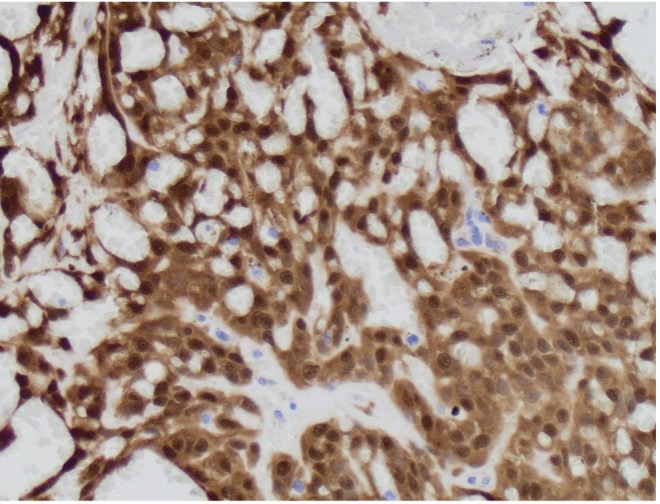

Case History:

A 64 year-old man with history of clear cell renal cell carcinoma s/p nephrectomy (2021) presents with scrotal pain and firmness. Ultrasound reveals a 2 cm solid lesion. Serum tumor markers (hCG and AFP) were normal. The tumor was negative for SALL4, OCT3/4, AFP, and showed focal patchy positivity for pancytokeratin (focal). PAX8 was weakly positive. Additional stains are displayed in the pictures.